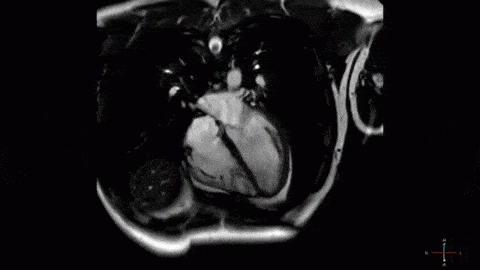

5. Так виглядає биття людського серця